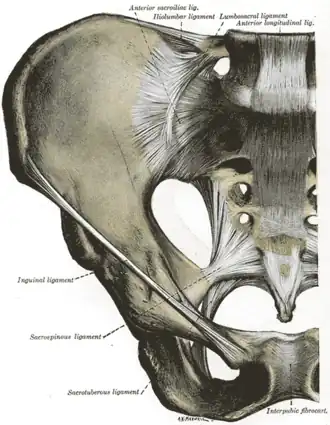

Articulations of pelvis. Anterior view.

Articulations of pelvis. Anterior view. -